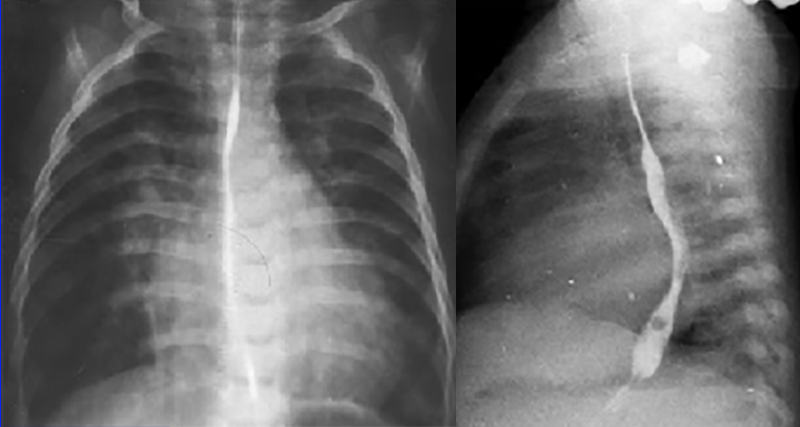

These chest X rays demonstrate left atrial enlargement, right and left ventricular enlargement and increased pulmonary arterial vascularity.

In the PA view, left atrial enlargement is reflected by elevation of the left main stem bronchus.

It is more definitively demonstrated in the lateral view by the posterior deviation of the barium filled esophagus.

The PA view also demonstrates right and left ventricular enlargement, based on the large cardiac shadow significantly greater than fifty percent of the thoracic diameter, extending both leftward and rightward.

Increased pulmonary arterial vascularity is reflected by the dilated central pulmonary arteries and the prominent distal arterial vascular markings.